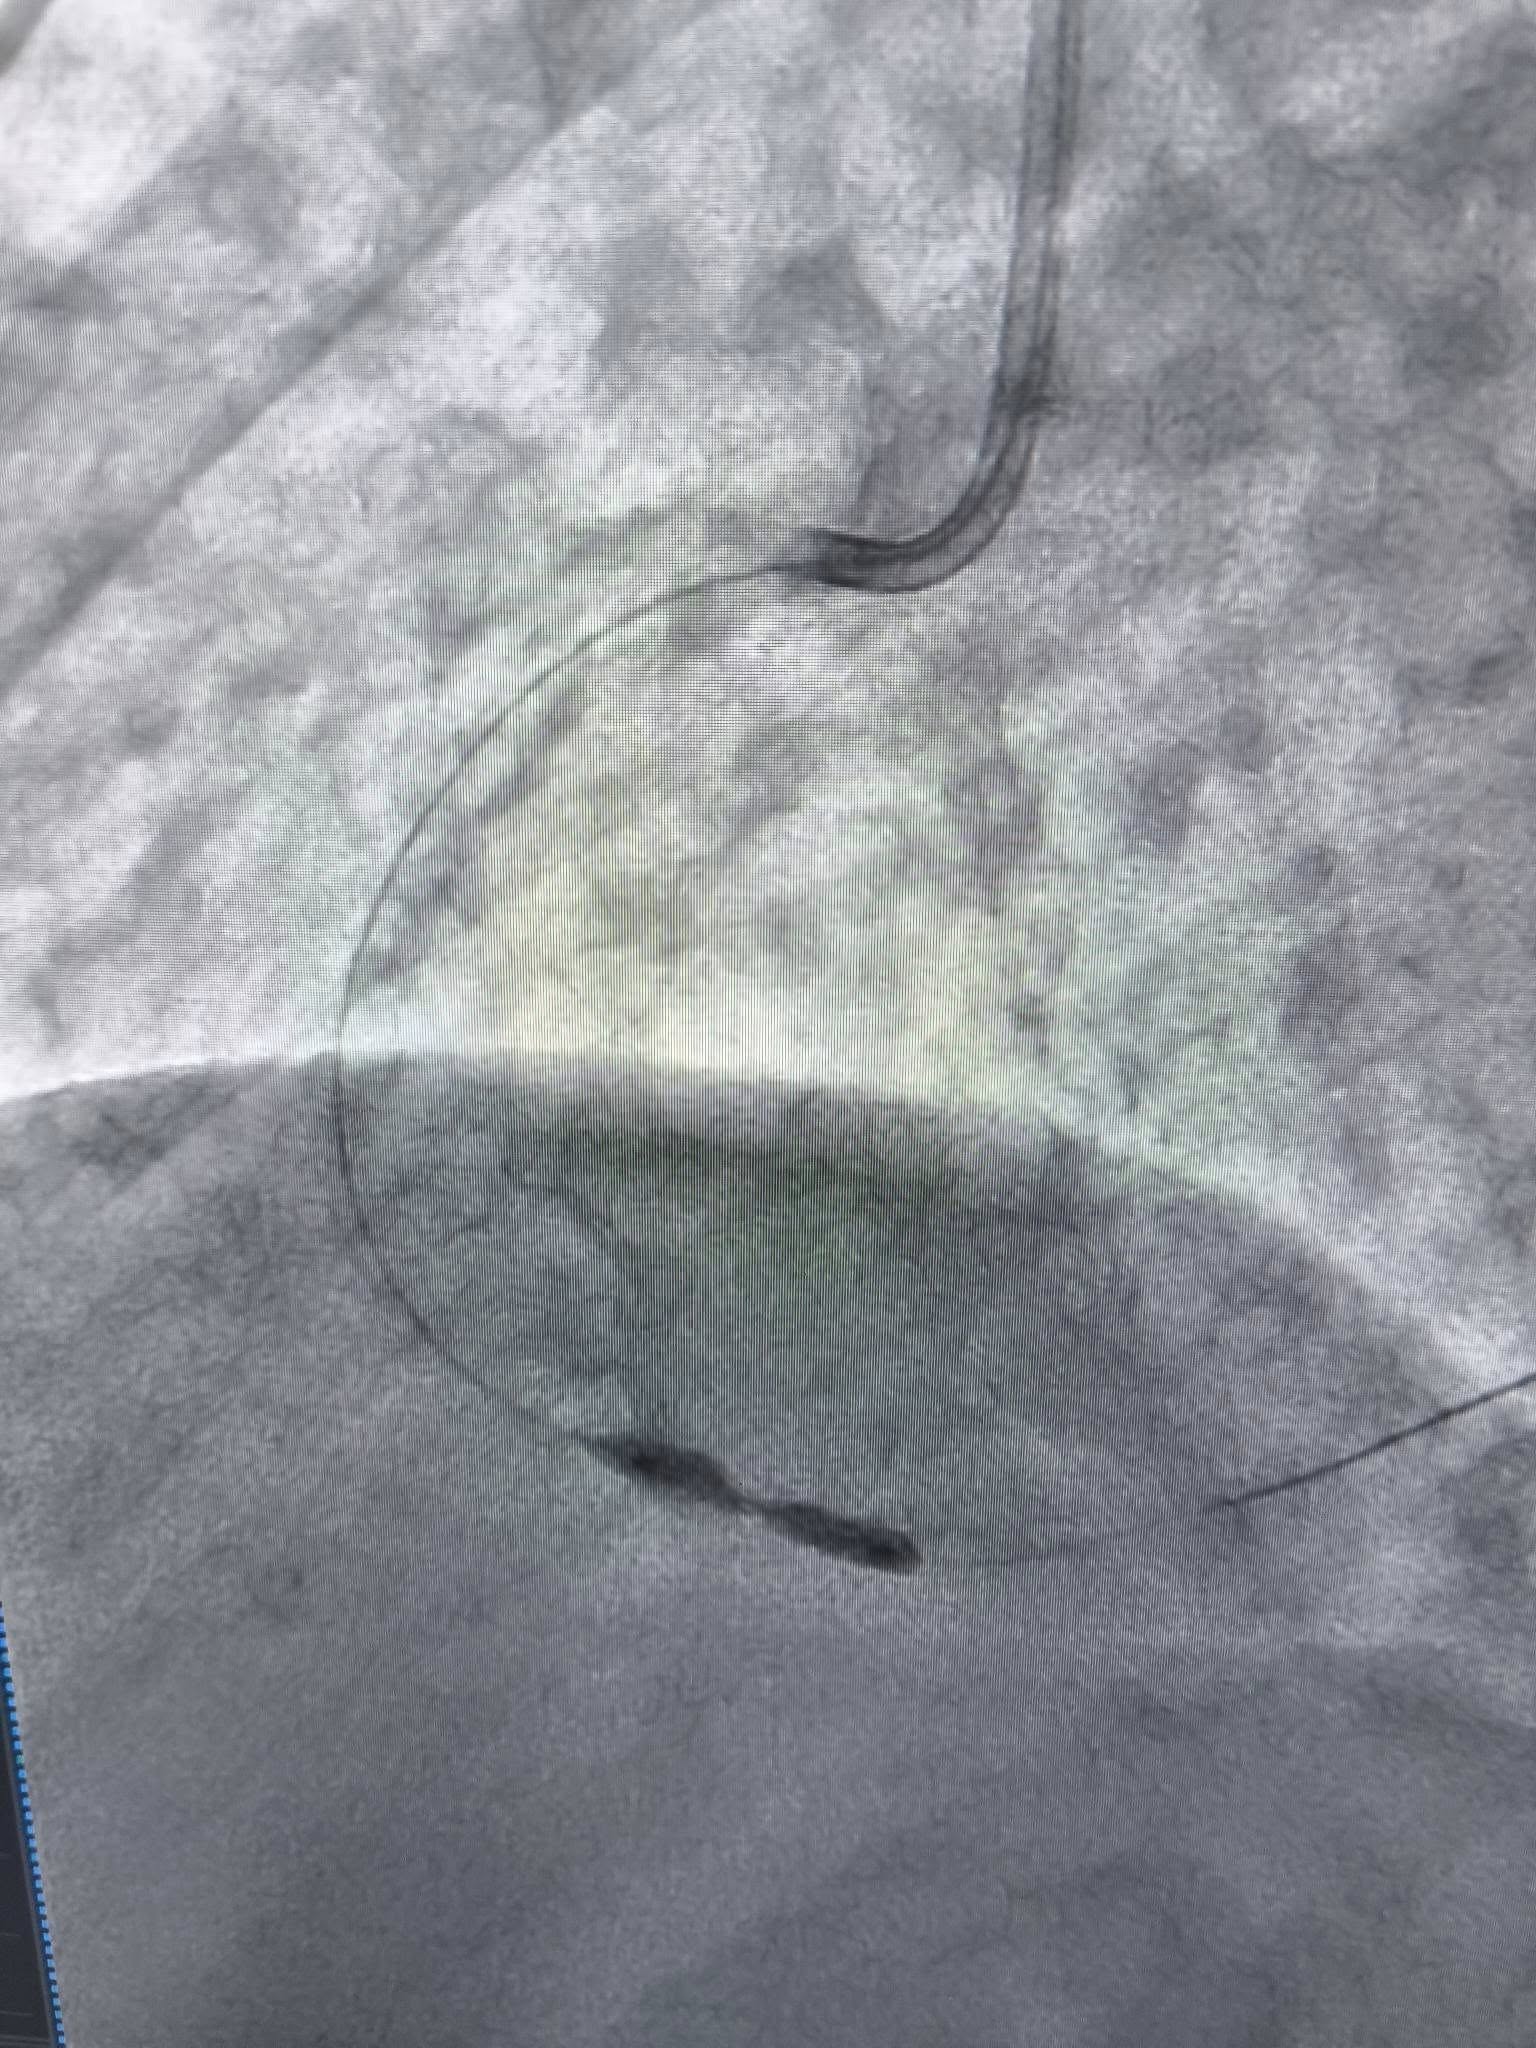

У таких ситуаціях на допомогу приходить ротаблятор – спеціальний пристрій із буром, покритим діамантовим напиленням.

Він дозволяє «модифікувати» кальциновану атеросклеротичну бляшку, фактично шліфуючи її та відновлюючи можливість для подальшого стентування судини.